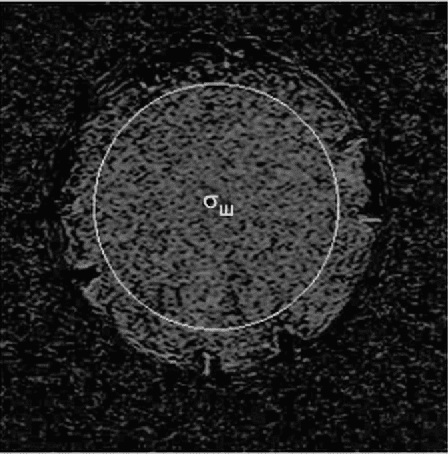

а) на одном из полученных изображений выделяют область интереса, включающую не менее 85% изображения фантома (см.

рисунок 2);

Рисунок 2 - МР-изображение для оценки уровня сигнала